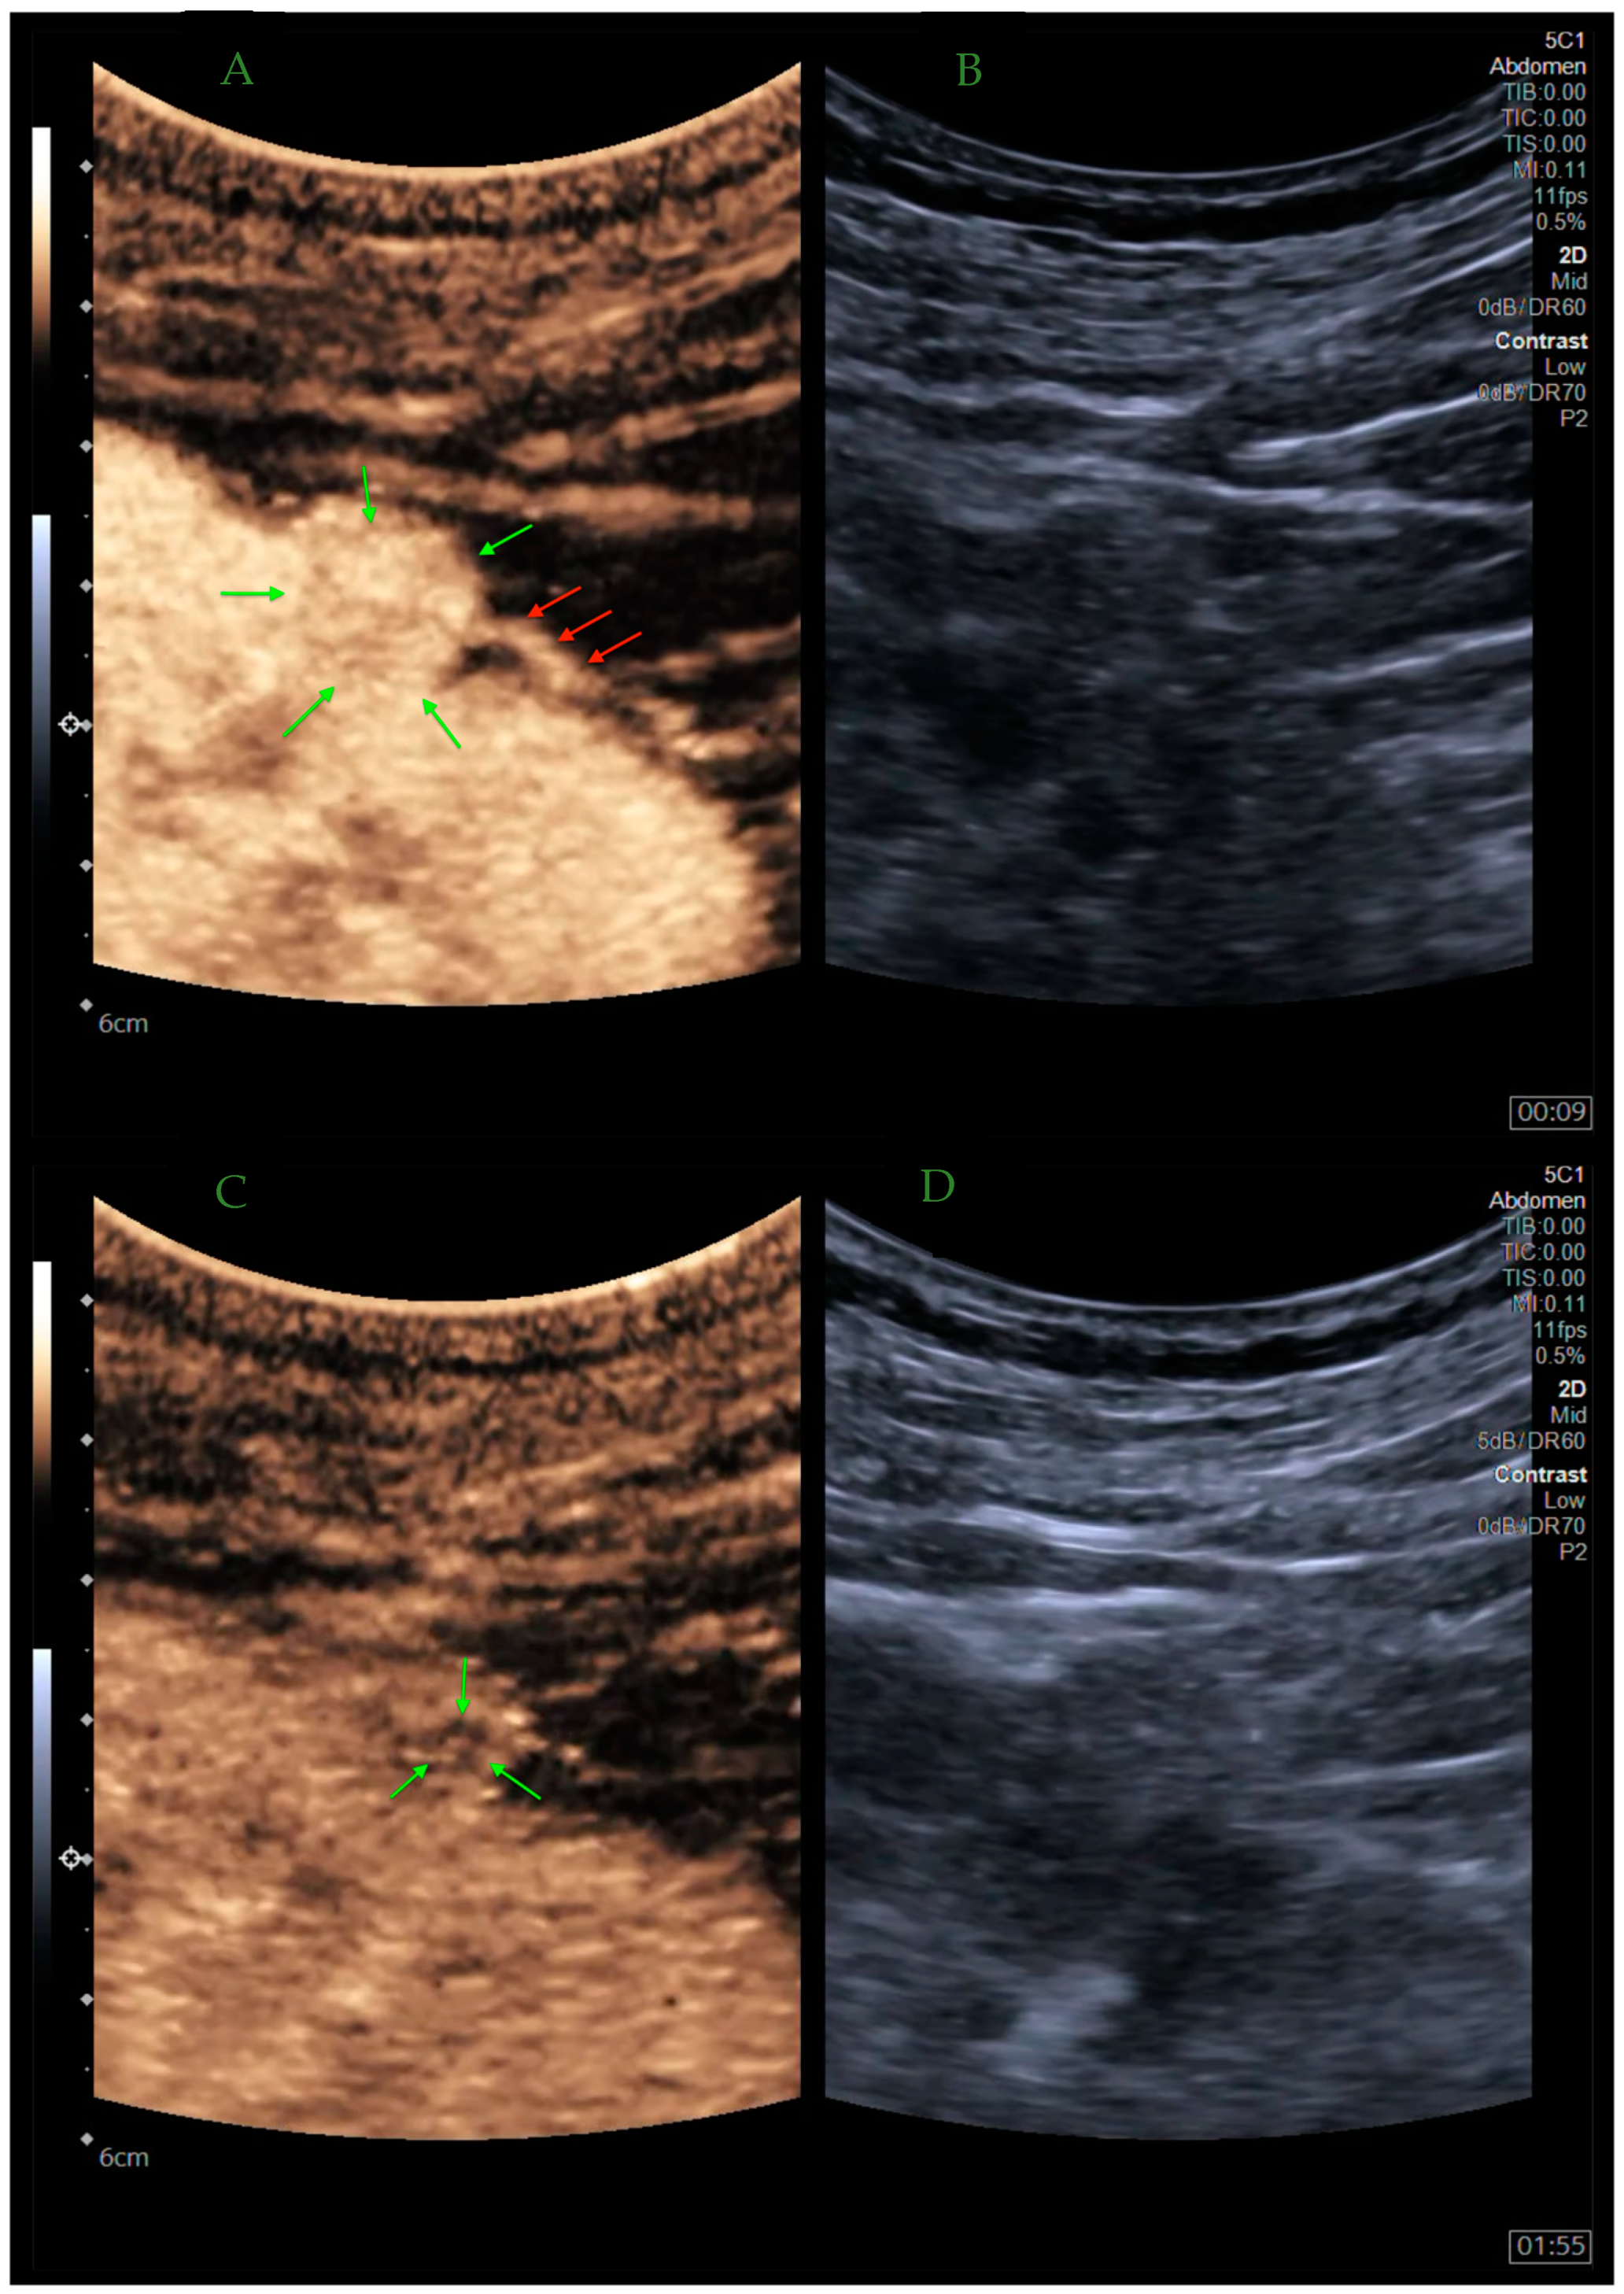

8. Monitoring Tumor Ablation